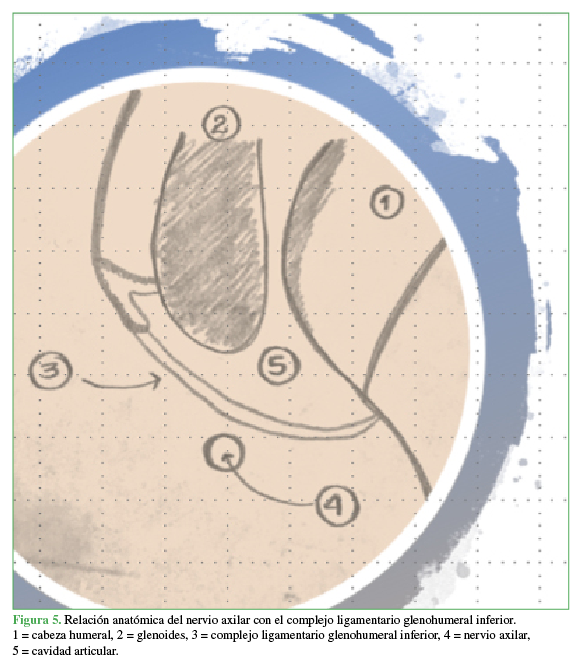

Lesión traumática del nervio axilar identificada luego de la reparación del manguito rotador. [Traumatic injury of the axillary nerve identified after rotator cuff repair]